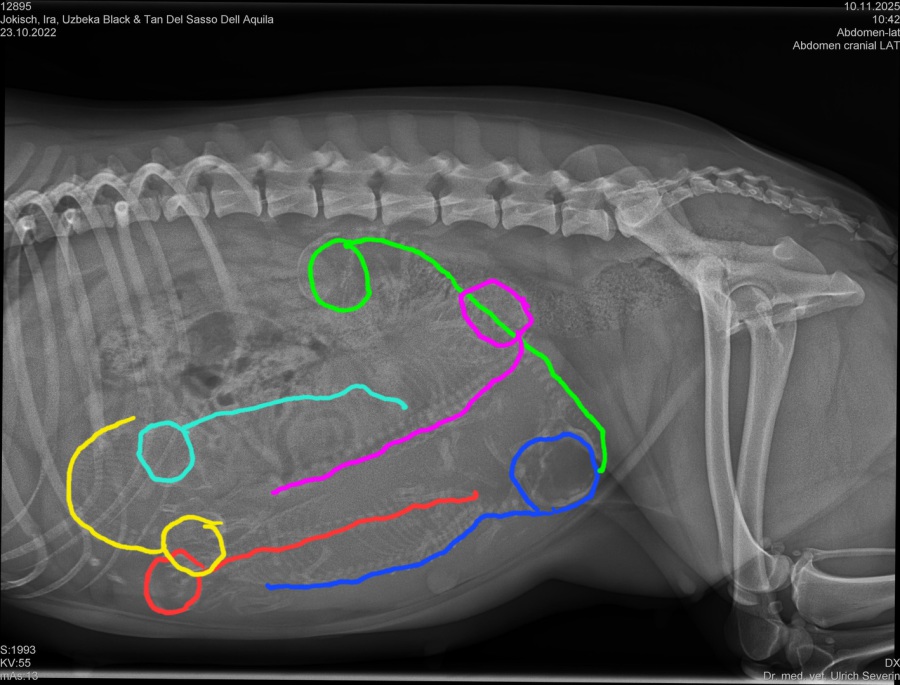

Wir waren am 10.11. beim Röntgen und konnten 6 kleine Welpen zählen.